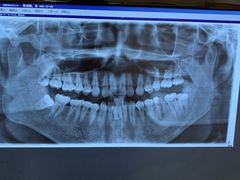

• 瑞尔齿科(上海长风大悦城店)

• -瑞尔齿科(上海长风大悦城店)